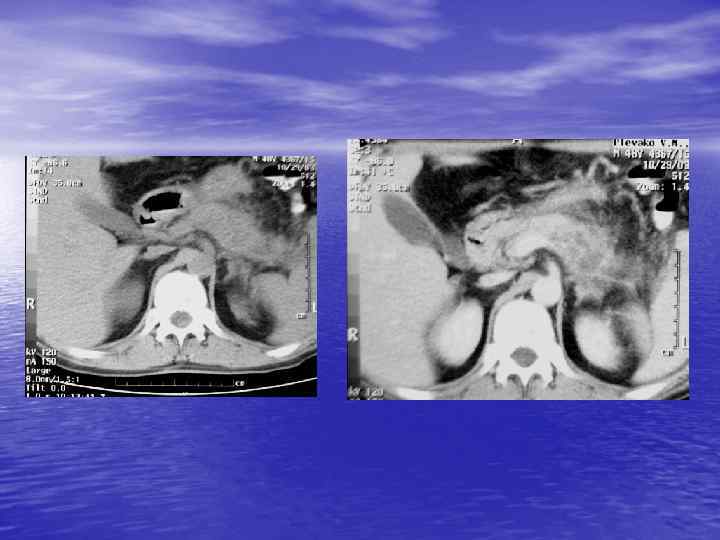

Структурный анализ Оценка основных макроскопических признаков: - положение - форма - размеры - характер контуров и структур патологически измененных участков

Структурный анализ

Денситометрический анализ Определение основных видов патологических образований: - обызвествленных - мягкотканных - жидкостных - жиросодержащих - воздухсодержащих

Денситометрия